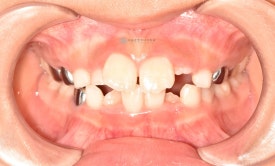

치료 전 - 위아래 심한 공간 부족이 관찰됩니다.

아이는 위 아래 심한 공간부족으로 인한 어린이덧니가 관찰됩니다. 공간부족으로 인해 앞니가 삐뚤빼뚤하게 나왔으며 곧 나올 위 두번째 앞니도 회전되어 맹출이 예상됩니다.

치료 전 - 위아래 심한 공간 부족이 관찰됩니다.아이는 위 아래 심한 공간부족으로 인한 어린이덧니가 관찰됩니다. 공간부족으로 인해 앞니가 삐뚤빼뚤하게 나왔으며 곧 나올 위 두번째 앞니도 회전되어 맹출이 예상됩니다.